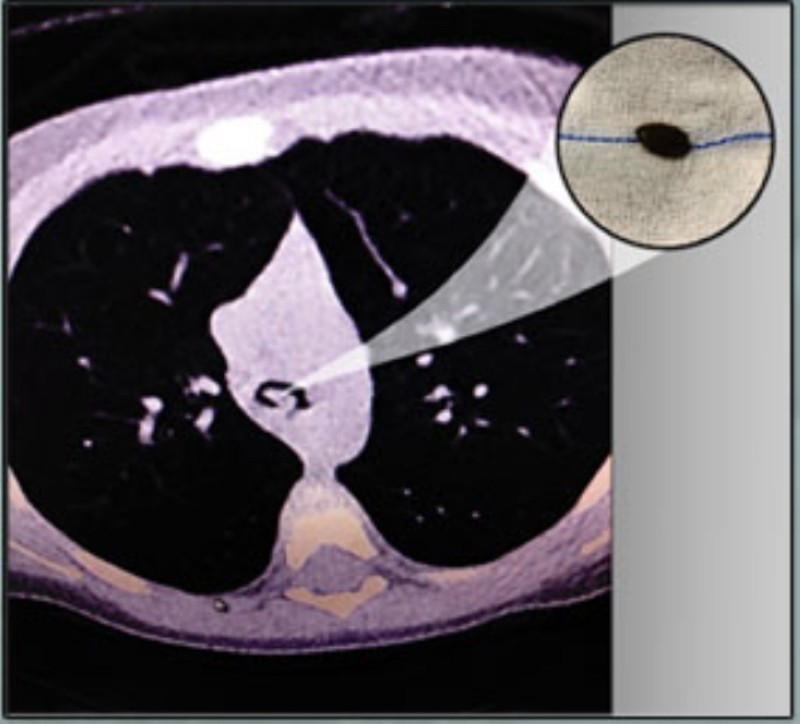

وبعد القيام بالفحوصات المخبرية والإشعاعية اللازمة تبين أن الجسم الغريب قد استقر في أسفل «الرغامي»، داخل القصبة الرئيسية للطفلة. ليتمكن الفريق الطبي من إجراء العملية، وذلك باستخدام المنظار القصبي وبشكل دقيق من استخراج الجسم الغريب وتكللت العملية بالنجاح.